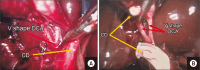

Results: Of the 375 patients, 26 (6.9%) had laparoscopic anatomical variations, of whom 19 (73.1%) had vascular variations and seven (26.9%) had ductal variations. The anatomical variations included the following: double cystic artery of separated origin, seven cases (26.9%); Moynihan's hump, six (23.1%); double cystic artery of single origin, four (15.4%); thin long cystic duct, four (15.4%); subvesical duct, three (11.5%); and cystic artery hocking the cystic duct, two (7.7%).

Conclusion: Biliary anatomical variations can be expected in any dissected zone. Most of the detected variants were associated with the cystic artery. An overlooked accessory cysto-biliary communication can cause complicated biliary leakage. A surgeon's skills and knowledge of laparoscopic anatomical variants are essential for performing a safe laparoscopic cholecystectomy.